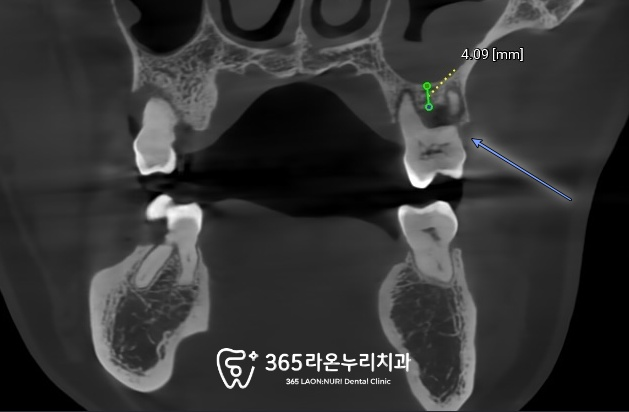

식립 전

CT를 찍어 뼈이식 계획과

식립 위치를 미리 계획하게 되는데요.

2025.4.13

CT를 봐도 치조골이 많이 녹아있고

남아있는 뼈가 4mm 정도 있는것을

세교동 치과 에서 확인할 수 있었는데요.

임플란트 길이는 짧은것은

7mm~15mm 정도 됩니다.

(물론 더 짧은 short size 도 있습니다.)

그래서 상악동을 들어 뼈를 채워주고

픽스처가 들어갈 수 있는

충분한 공간을 만들어야 됩니다.